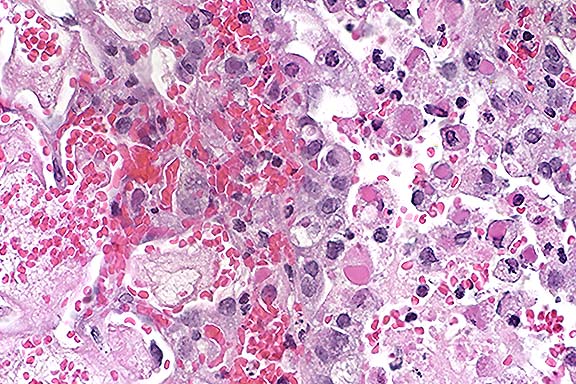

Case 16-1. Eye. The iris is expanded by an influx of lymphocytes, plasma cells, and histiocytes. Eosinophilic, proteinaceous exudate is in the anterior chamber (right). 20X

AFIP Diagnosis: Eye: Anterior uveitis, lymphoplasmacytic and histiocytic, diffuse, moderate, with corneal edema, peripheral keratitis, scleritis, episcleritis, and proteinaceous exudate in anterior, posterior, and vitreous chambers, Beagle, canine.

Conference Note: Conference participants noted mild attenuation of the filtration angles, which likely caused the increased intraocular pressure by interfering with fluid drainage from the anterior chamber. However, histologic changes compatible with glaucoma (i.e. atrophy of inner retinal layers, optic disc cupping) are not present.